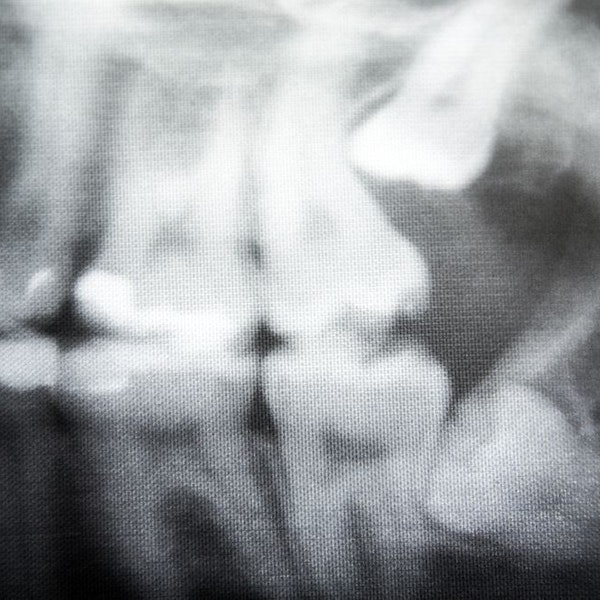

Pricing for wisdom teeth removal varies depending on the level of impaction. You will first come in for a consult that includes an $80 panoramic X-ray and a $20 exam fee. Based on this information, our dentist can estimate the cost of your procedure. Sedation is available for an additional fee. Our dental practice accepts most insurance plans, and we also offer CareCredit® financing to help break your cost into manageable, monthly payments.